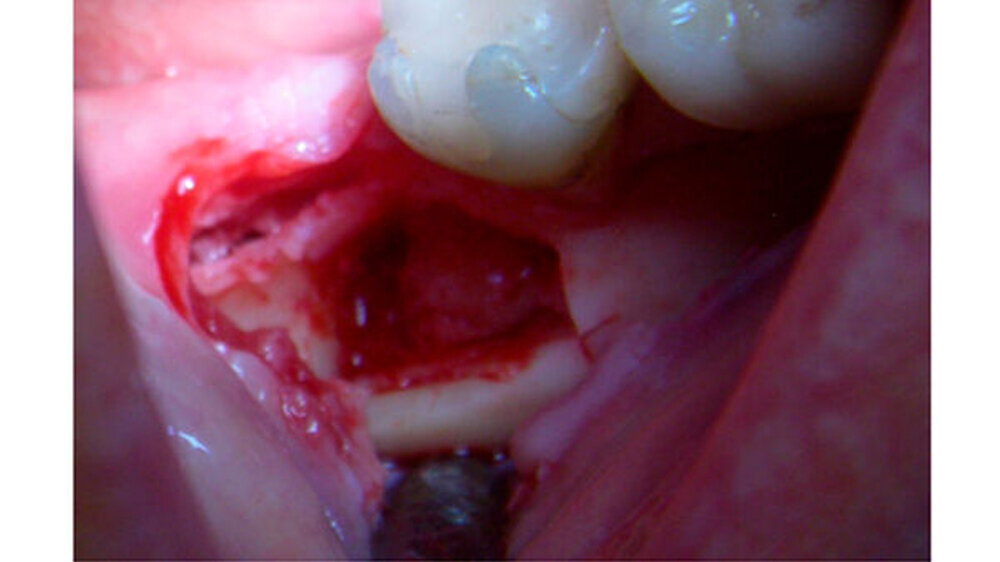

Der Zahn 47 reagierte positiv auf den Vitalitäts-/ Sensibilitätstest. Eine dreidimensionale Bildgebung musste von der Patientin aus wirtschaftlichen Gründen abgelehnt werden. Die Verdachtsdiagnose: ein Osteom oder ein Zementom. Zur explorativen Probeexzision wurde nach minimalinvasiver Schnittführung ein Knochendeckel präpariert, was eine berührungslose Darstellung der knöchernen Veränderung erlaubte. Weil die Veränderung sehr hart und spröde war, konnte sie nicht in toto entfernt werden.

Klinisch zeigte sich, dass die knöcherne Veränderung nicht mit Blutgefäßen durchsetzt war. Erst nach vollständiger Entfernung konnte in der Defekttiefe aus der angrenzenden lingualen Spongiosa eine Blutung provoziert werden. Histologisch wurde ein Osteom aus kompaktem, regressiv verändertem Lamellenknochen mit überwiegend leeren Osteozytenlakunen sowie sehr vereinzelt unreifes Osteoid mit aktivierter Bindegewebszone nachgewiesen.